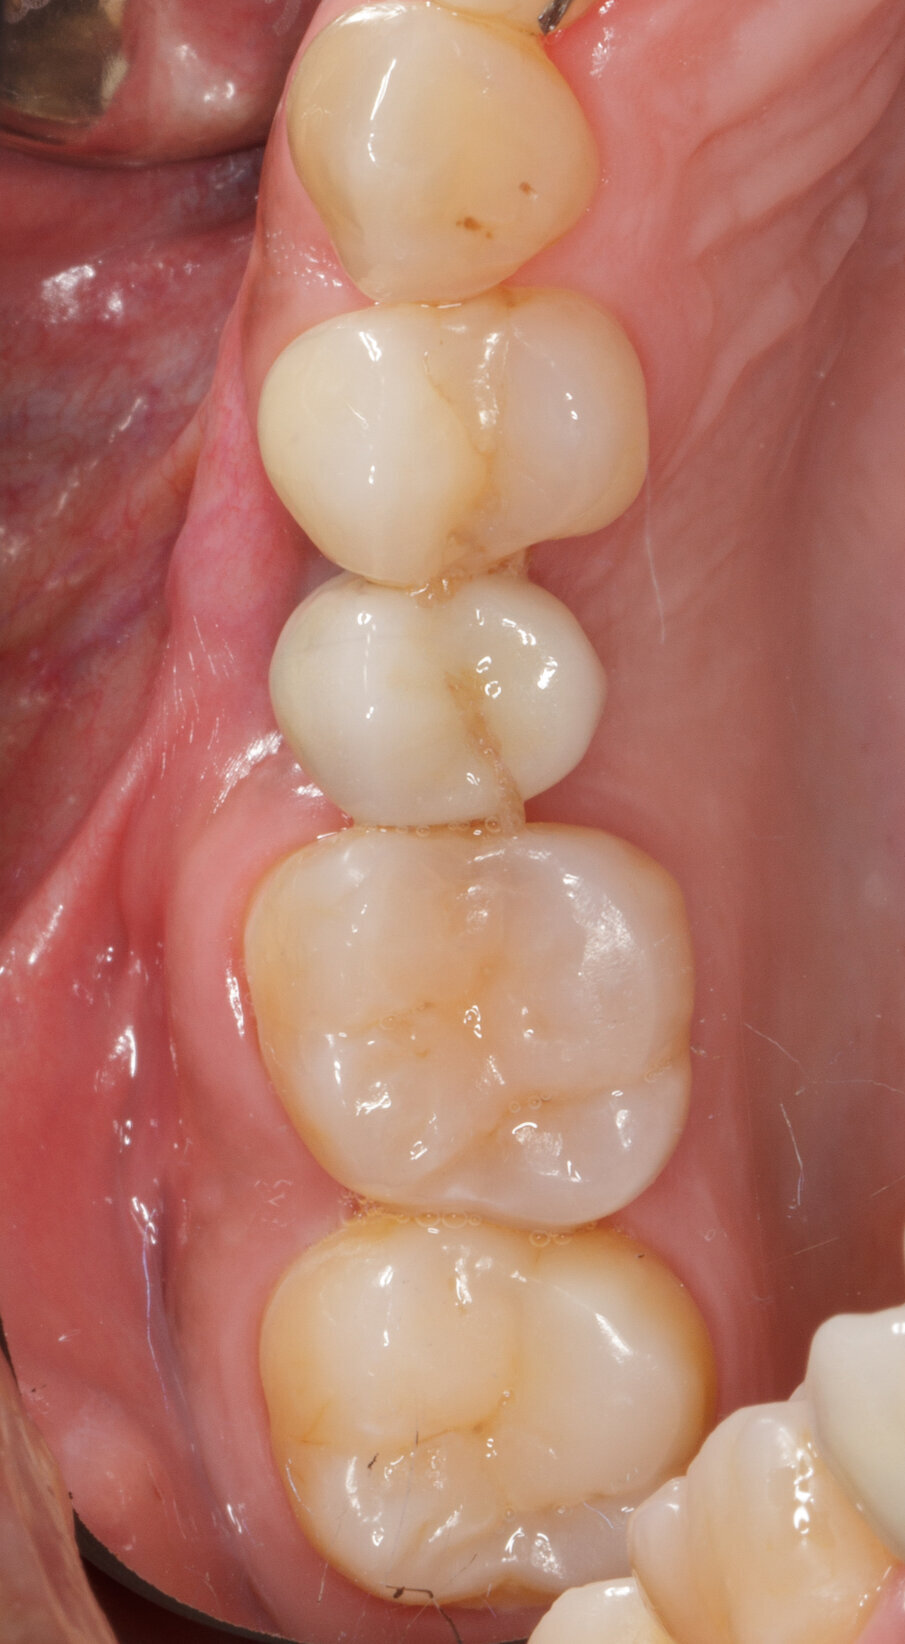

Caso clinico Viene presentato un caso clinico di GBR per la ricostruzione volumetrica di una cresta ossea atrofica mascellare con inserimento di biomateriale osseo di natura eterologa (OsteoBiol Gen-Os) e di una lamina corticale soft collagenata (OsteoBiol Lamina Soft) stabilizzata sulla sede del difetto osseo con utilizzo di colla di fibrina (Tisseel, Baxter) e con 2 chiodini di fissazione crestali. La paziente N.H. di anni 42, sesso femminile, non fumatrice, ASA 1, si presentò alla mia osservazione per la sostituzione di un elemento dentale, 2° premolare superiore destro, estratto più di 15 anni prima (Figg. 2, 3). Dall’esame clinico si osserva un marcato riassorbimento in senso orizzontale del sito edentulo, lo stato dei tessuti gengivali è di salute, non vi sono lesioni parodontali sui denti contigui. L’esame CBCT conferma la perdita di oltre il 50% del tessuto osseo vestibolare pur rimanendo conservata l’altezza verticale della cresta (Fig. 4).

Fig. 3 - Situazione iniziale. Vista occlusale.

Fig. 4 - Forte perdita ossea vestibolare.